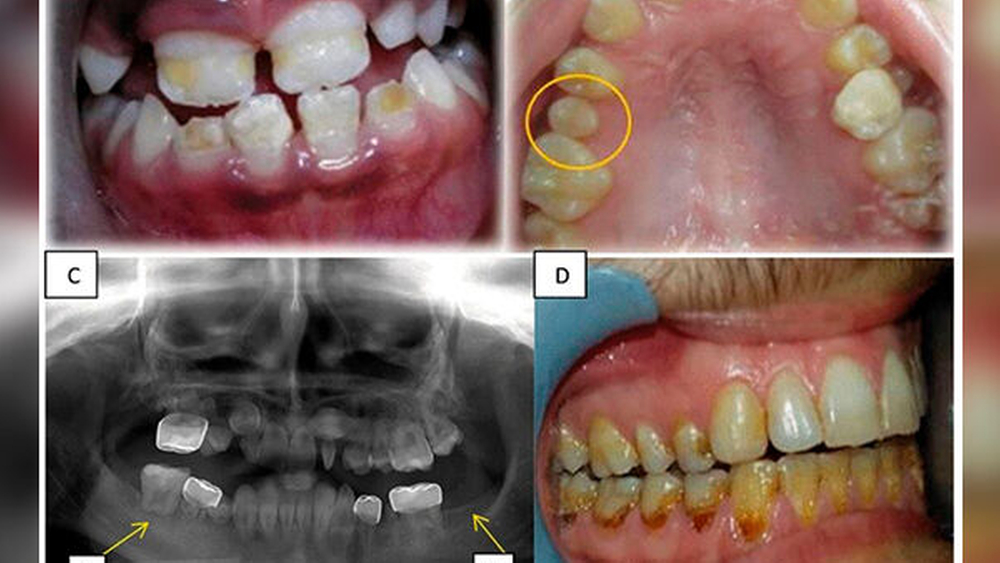

Der Studie zufolge sind die ersten Anzeichen von Zahnentwicklungsstörungen frühestens zwei Jahre nach der Krebsbehandlung zu erwarten. Zu den dokumentierten Anomalien gehörten Hypomineralisierung, Hypoplasie, Mikrodontie und Hypodontie. Zahnwurzelanomalien waren die am häufigsten auftretende Veränderung.

Darüber hinaus gab es auch Fälle von übermäßiger Retention von Milchzähnen, Impaktion, vorzeitigem Durchbruch, verminderter Beweglichkeit des Kiefergelenks, Kieferklemme und Gesichtsdeformitäten. Die signifikantesten geschlechtsspezifischen Unterschiede bei den Zahnanomalien war eine höhere Inzidenz von Mikrodontie bei den Mädchen und eine höhere Prävalenz kariöser Zähne bei den Jungen.